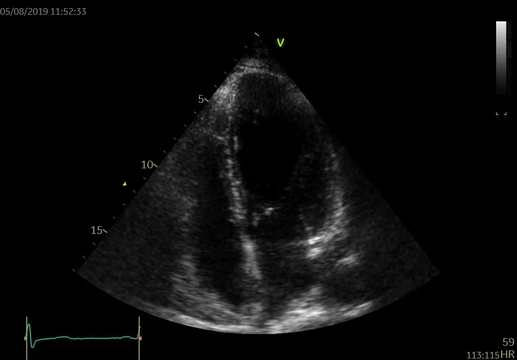

Pacientka byla dále pravidelně sledována, s postupným zlepšováním klinického stavu i echokardiografického nálezu. Po 12 měsících léčby je nemocná ve funkční třídě NYHA I–II, bez známek městnání i po vysazení furosemidu. Echokardiograficky došlo k normalizaci velikosti i systolické funkce LK (LVEDD 52 mm, EF 55 %), přítomna je lehká diastolická dysfunkce s normálními plnicími tlaky levé komory a pouze lehká mitrální a trikuspidální regurgitace a hraniční velikost levé síně (video 5). Laboratorně jsou hodnoty iontogramu a kreatininu v normě, došlo k výraznému poklesu NT-proBNP na 290 ng/l.

Video 5. Echokardiografické vyšetření po 12 měsících. 5A – reverzní remodelace LK s normální velikostí a systolickou funkcí, EF 57 %, 5B – lehká mitrální regurgitace